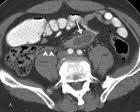

Acute appendicitis, which occurs when the appendix — a small, tube-like structure attached to the large intestine — becomes blocked and inflamed, requires prompt surgical removal. Left untreated, an inflamed appendix will eventually perforate, or burst, spilling infectious materials into the abdominal cavity, which can be life-threatening. In the less common chronic and recurrent appendicitis, patients experience milder symptoms that may come and go. According to the National Institutes of Health, appendicitis can affect anyone, but is more common among people 10 to 30 years old. Appendicitis leads to more emergency abdominal surgeries than any other cause.

Of the study’s 2,283 patients, 516, or 23 percent, had CT findings that indicated a probable or definite appendicitis. Of those 516 patients, 450 (87 percent) had their appendix surgically removed within four days. Ninety-five percent of those cases were confirmed as acute appendicitis.

Thirteen (three percent) of the 516 patients with positive CT findings did not receive immediate surgical treatment because their symptoms — including a normal appetite, absence of nausea and vomiting, normal white blood cell count and mild or resolving pain — were atypical for acute appendicitis. Of those, five (38 percent) ultimately had their appendix removed after seeking treatment for the same symptoms an average of four months later. Appendicitis was confirmed in all cases.